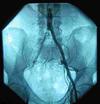

Femoral triangle